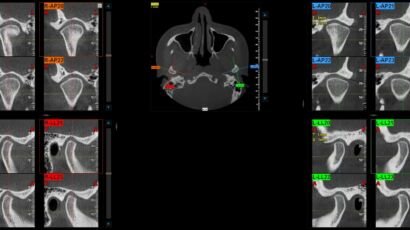

Un examen de tomografía computarizada (TAC) macizofacial es una herramienta diagnóstica esencial en la…

El examen de TAC macizofacial, o tomografía axial computarizada macizofacial, es una técnica de…